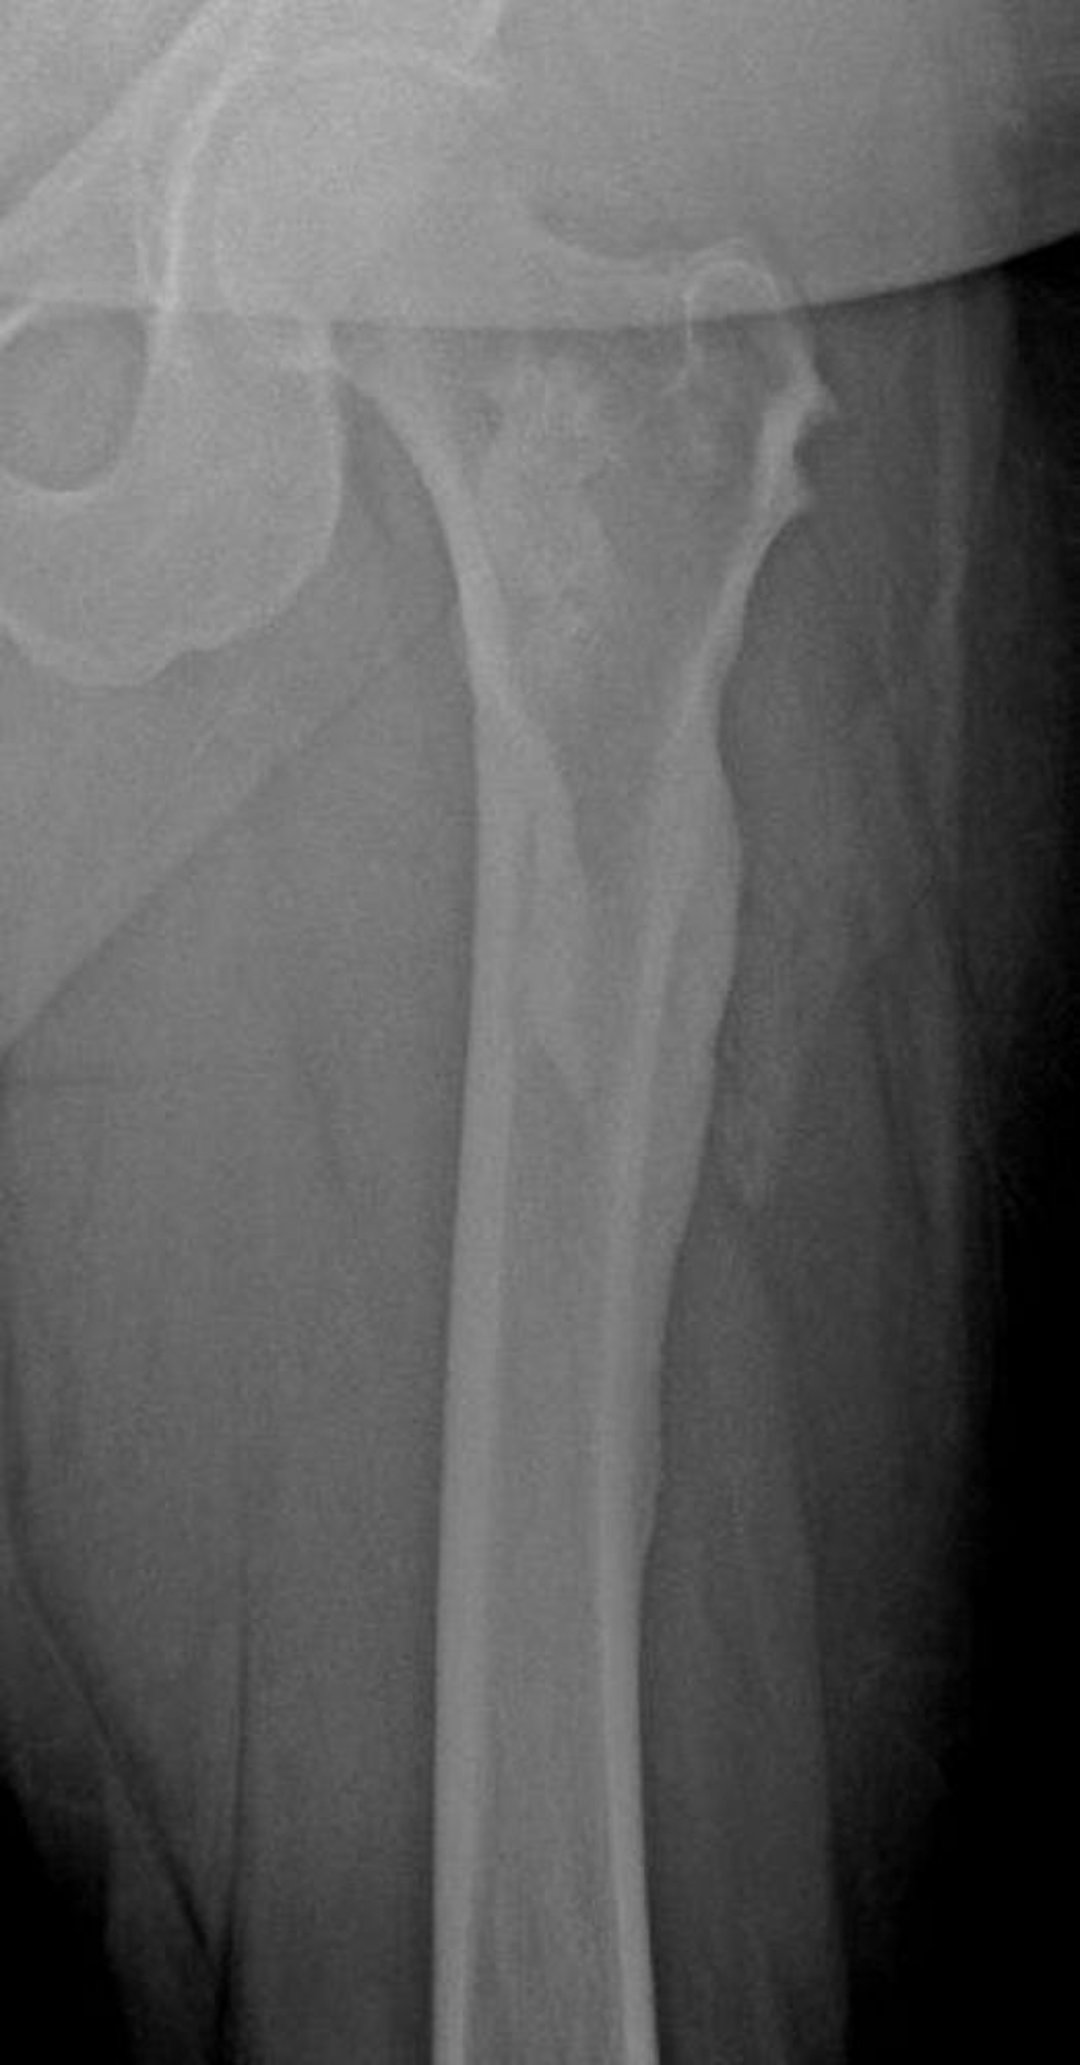

Mélorhéostose (gouttes de cire)

Cette radiographie montre l'aspect en "cire de bougie qui coule" de la mélorhéostose dans le fémur; il est particulièrement visible au niveau du cortex fémoral latéral.

Image courtoisie de Michael J. Joyce, MD, and David M. Joyce, MD.